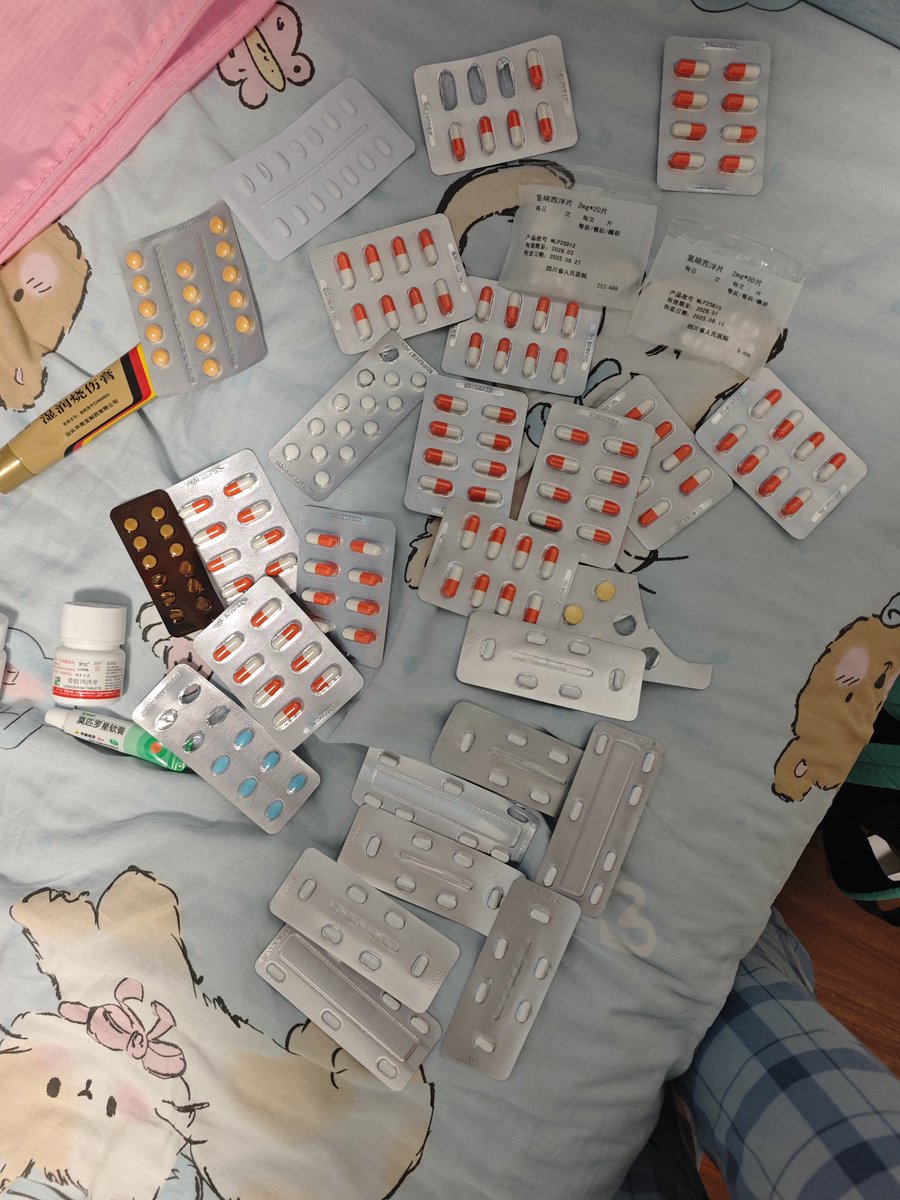

呱呱呱 @6xocxRPFdjF84Vo@AnIncandescence 啊啊啊我现在看见药片就想吐🤮,可能因为我之前把50片碳酸锂含化了的那个味道终生难忘